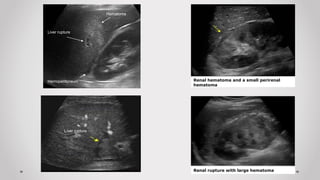

 Mặt cắt 2: liên sườn Phải

Trả lời các câu hỏi:

- Có dịch rãnh gan-thận (Morrison)?

- Chấn thương gan (P)? Thận (P)?

 Dịch rãnh Morrison

 Dịch rãnh Morrison + Dịch trên gan

Liver rupture

Hemoperitoneum

Hematoma

Renal hematoma and a small perirenal

Renal rupture with large hematoma